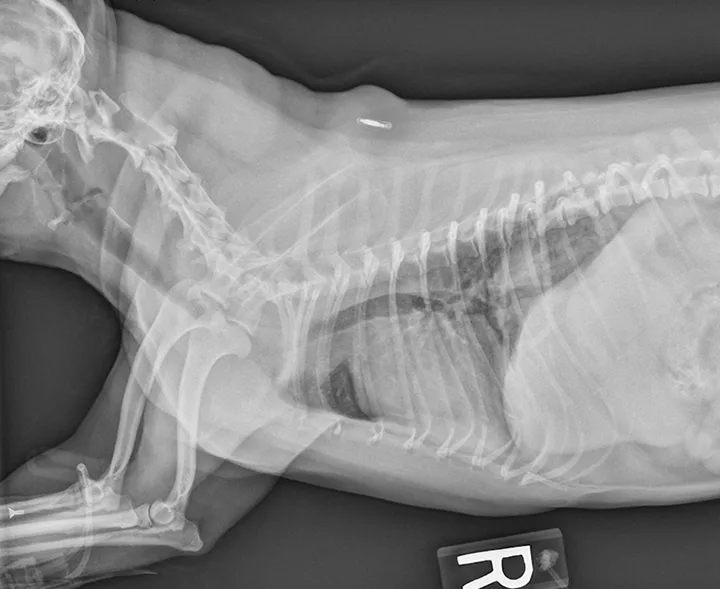

An 8-year-old neutered male Yorkshire terrier is presented for respiratory distress. The patient had been exhibiting a loud, progressive, honking cough for 18 months before presentation. The owners had attempted nebulization and coupage at home without improvement. Physical examination reveals a distressed patient with a respiratory rate of 60 breaths/min, loud upper airway stridor and stertor, and coughing. Temperature is 103.9F (39.9C), heart rate is 160 bpm, and mucous membranes are a muddy/cyanotic color. Oxygen is administered, and the patient improves enough for lateral radiography; radiographs reveal a grade III to IV tracheal collapse at the thoracic inlet and a mild interstitial pattern, most prominent in the caudodorsal region of the lungs (Figure 1).

Radiograph showing grade III to grade IV tracheal collapse and a mild interstitial pattern